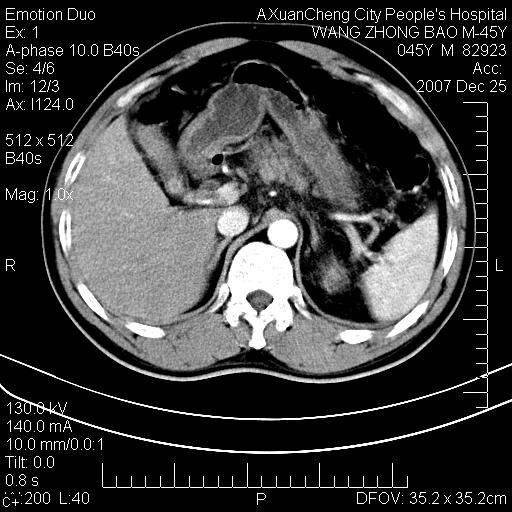

以下是引用卜一在2007-12-25 14:07:00的发言:[br]胰头钩部略增大,与十二指肠壶腹部关系密切,其内明显见软组织密度肿块,明显强化,但肠壁较光滑 柔软。考虑:炎性增生!建议消炎后复查!待除外壶腹部腺癌!

以下是引用zjzjr在2007-12-25 13:35:00的发言:[br]考虑正常的十二指肠乳头部,建议胃镜检查.

以下是引用qiuleiyu在2007-12-25 18:14:00的发言:[br]胰腺增大,周边渗出改变,肾前筋膜明显增厚,示少量积液.胆囊壁毛糙,周边少许渗出,胆总管壁厚,异常强化,然扩张不明显.结合病程急短;考虑;胆管炎,胆囊炎,胆源性胰腺炎可能大,请结合实验室检查及随访.

以下是引用lisihao在2007-12-25 14:23:00的发言:[br]急性水肿型胰腺炎[br]依据:1、胰腺弥漫性肿大,边缘稍毛糙;[br] 2、双侧肾周筋膜增厚,尤以左侧为甚(重要征象)[br] 3、双侧后胸膜增厚(刺激性炎症);[br] 4、结合病史,查血尿淀粉酶应该可以确诊。